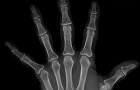

64 year old female presents with c/o persistent vs recurrent mass in her L ring finger. She recently had an excisional biopsy performed by another surgeon, who was performing a first dorsal compartment release on her as well. NVI

Zoom image: Radiological image Radiological image.